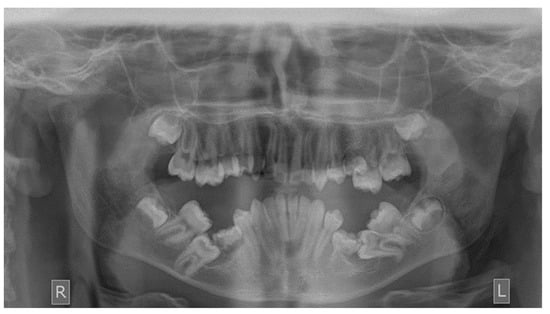

As far as the etiology of impaction is concerned, 205 patients presented one factor responsible for impaction, while 7 presented two. Table 2 shows the ectopic eruption path as the most frequent factor that was reported in 5.29% of total patients examined and mostly reported in maxillary canines. The next most common etiology was the loss of space in the arch (2.50%), followed by the ankylosis of deciduous teeth (1.71%). Concerning the rest of the causative factors, supernumerary teeth other than deciduous were observed in 1.29% of the patients, while the mesiodens was the most frequent supernumerary permanent tooth. In total, 1.21% of the sample presented tumors such as odontoma and osteoma, more often in association with maxillary central incisors. Supernumerary deciduous teeth affected 0.86% of the patients examined, while the ankylosis of permanent teeth was presented in 0.79 of the cases. The maxillary second premolars were the most frequently impacted teeth due to ankylosis. The least common etiology of impaction proved to be the primary failure of eruption, with 3 reported cases out of 212 patients, that following the radiographic examination were all confirmed by genetic tests. Panoramic radiographs indicated for some local etiological factors are presented below (Figure 1, Figure 2, Figure 3 and Figure 4).

Figure 1. Primary failure of eruption of upper and lower molars.